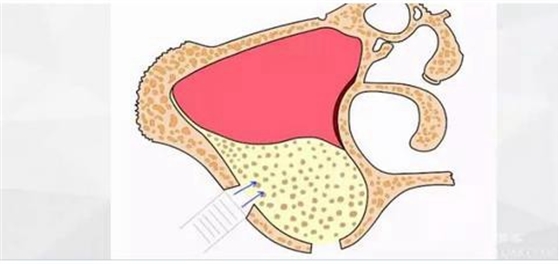

擴(kuò)大窗口,此時(shí)因?yàn)樯项M竇膜已經(jīng)與骨壁分離,所以打磨時(shí)不會(huì)損傷到膜。

此時(shí)頰側(cè)竇膜與骨壁已經(jīng)分離,無需擔(dān)心開窗損傷竇膜。使用環(huán)切鉆以小洞口為中心開窗,轉(zhuǎn)速500轉(zhuǎn),為了保證安全,可以將種植機(jī)調(diào)成反轉(zhuǎn)模式,一樣有強(qiáng)大的切割效率。